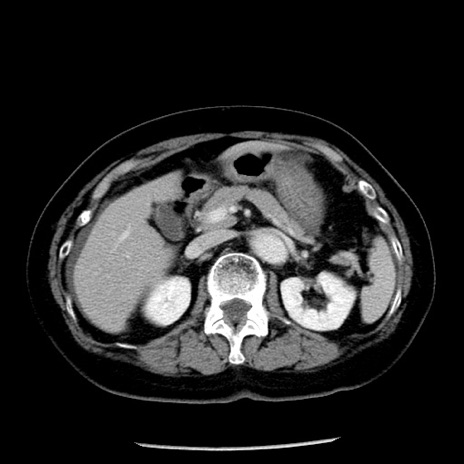

冠状断像